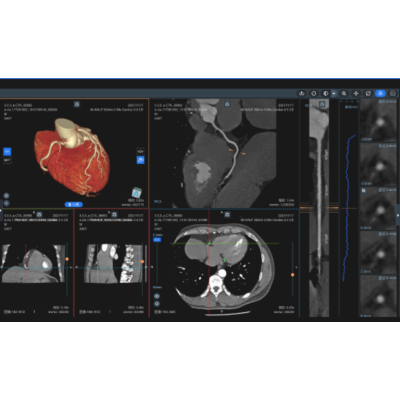

冠脉CTA辅助分析

全自动冠脉CTA三维重建、分析;精确冠脉狭窄评估;

心肌病变辅助诊断

应用MR影像,针对心脏MR长轴2腔、3腔、4腔,短轴电影序列等多模态影像数据,快速完成心脏MR影像定量分析,输出射血分数、容积、排空率、充盈率等多项心功能指标,智能评估左心室各段心肌运动功能;同步实现心肌梗死、扩张性心肌病、肥厚型心肌病等心肌病变辅助诊断。